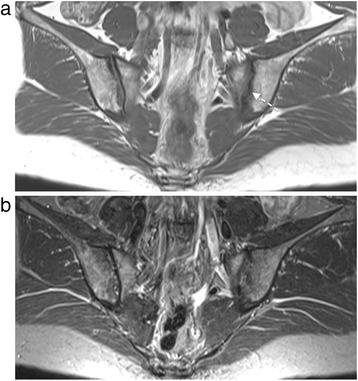

Bone marrow edema (BME) was assessed on short tau inversion recovery (STIR) scans from 185 patients with nr-axSpA, by two independent readers at baseline using the Spondyloarthritis Research Consortium of Canada (SPARCC) score. Structural lesions were evaluated on T1 weighted spin echo scans, with readers blinded to STIR scans, using the SPARCC MRI SIJ structural score. Disease characteristics and structural lesions were compared in patients with SIJ BME (score ≥2) and without SIJ BME (score <2).

Both SIJ BME and structural lesions scores were available for 183 patients; 128/183 (69.9%) patients had SIJ BME scores ≥2 and 55/183 (30.1%) had scores <2. Frequencies of MRI structural lesions in patients with vs without SIJ BME were: erosions (45.3% vs 10.9%, P < 0.001), backfill (20.3% vs 0%, P < 0.001), fat metaplasia (10.9% vs 1.8%, P = 0.04), and ankylosis (2.3% vs 1.8%, P = ns). Significantly more patients with both SIJ BME and structural lesions were male and/or HLA-B27 positive than patients with only SIJ BME. Mean (SD) spinal scores (23 discovertebral units) were significantly higher in patients with SIJ structural lesions than without: 6.5 (11.5) vs 3.3 (5.1), respectively, P = 0.01.

In patients with nr-axSpA, SIJ structural lesions, particularly erosions, may be present on MRI when radiographs are normal or inconclusive, even in patients negative for MRI SIJ inflammation. They may reflect more severe disease with greater spinal inflammation.